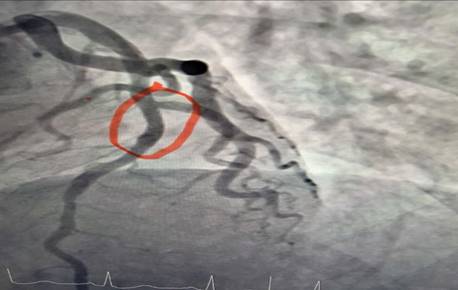

Hình ảnh nhồi máu cơ tim gây tắc 95% đoạn 1 động mạch liên thất trước

Ê-kíp bác sĩ khoa Nội tim mạch đã tiến hành chụp động mạch vành kết quả cho thấy: nhánh động mạch thủ phạm gây Nhồi máu cơ tim cấp là đoạn 1 động mạch liên thất trước hẹp 95%. Bệnh nhân đã được can thiệp nong và đặt Stent động mạch vành giúp tái thông dòng máu nuôi tim, hạn chế tối đa tổn thương cơ tim và các biến chứng nguy hiểm. Sau can thiệp mạch vành tái thông tốt, tình trạng người bệnh ổn định, các triệu chứng đau ngực giảm rõ rệt và tiếp tục được theo dõi, điều trị theo phác đồ chuyên môn.